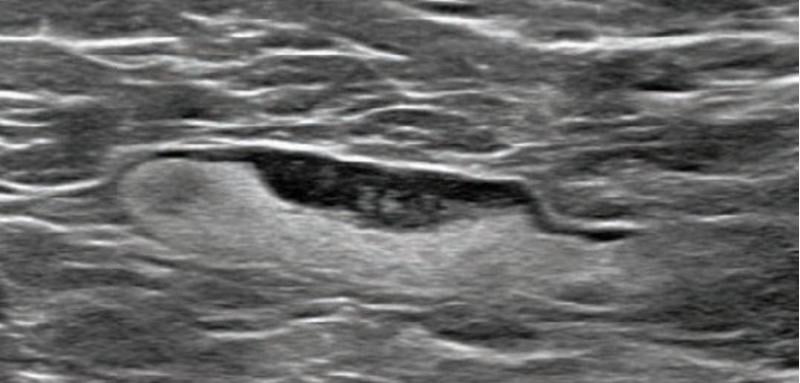

This photo gallery shows the variety of radiological presentations of COVID-19 (SARS-CoV-2) in medical imaging, including computed tomography (CT), radiograph X-rays, ultrasound, echocardiograms and magnetic resonance imaging (MRI). The radiology images show examples of typical COVID pneumonia in the lungs and the numerous complications the virus causes in the body in multiple organs, including the brain, kidneys, heart, abdomen and vascular system.

Ultrasound, especially hand-held ultrasound imaging devices, have become a primary imaging modality for novel coronavirus because of the ease to bag the device and sterilize it after use. CT and mobile X-ray systems are also used as front-line imaging systems for COVID-positive or suspected COVID patients.